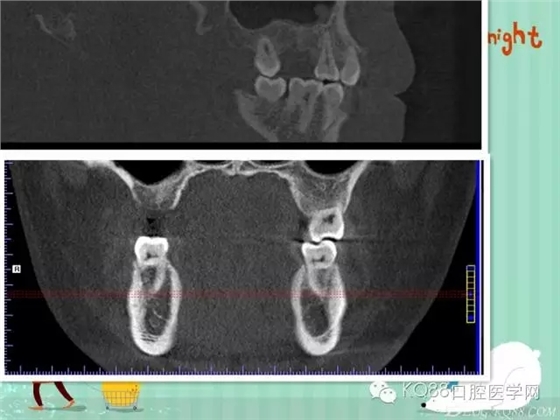

下面是拔牙后三個(gè)月的CBCT。垂直骨高度約6.7mm。

另外一個(gè)切面。垂直骨高度不夠,準(zhǔn)備 :做內(nèi)提升,植骨,植入植體。